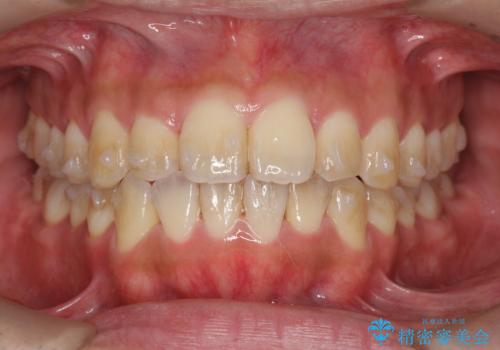

- 前歯のガタつきをきれいにしたい、と矯正治療を希望され来院されました。

マウスピース矯正インビザラインを用いてガタつきをきれいに並べていきます。

外側に傾斜していた前歯の角度も良くなり、「前歯の見た目が良くなった。」、と喜んでいただくことができました。